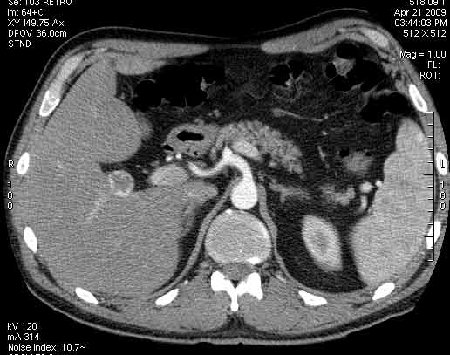

Сонограммы, КТ- артериальная, портальная и отсроченная паренхиматозная фазы

Сделали КТ (весьма похвальная тактика); по КТ: в артериальную фазу: периферическое усиление в виде сливающихся островков контраста, с центрипетальной направленностью. Венозная и отсроченная фаза-хорошее накопление контраста; образование практически изоденсно по отношению к паренхиме печени. Классика гемангиомы. Вуаля-диагноз на "тарелочке".